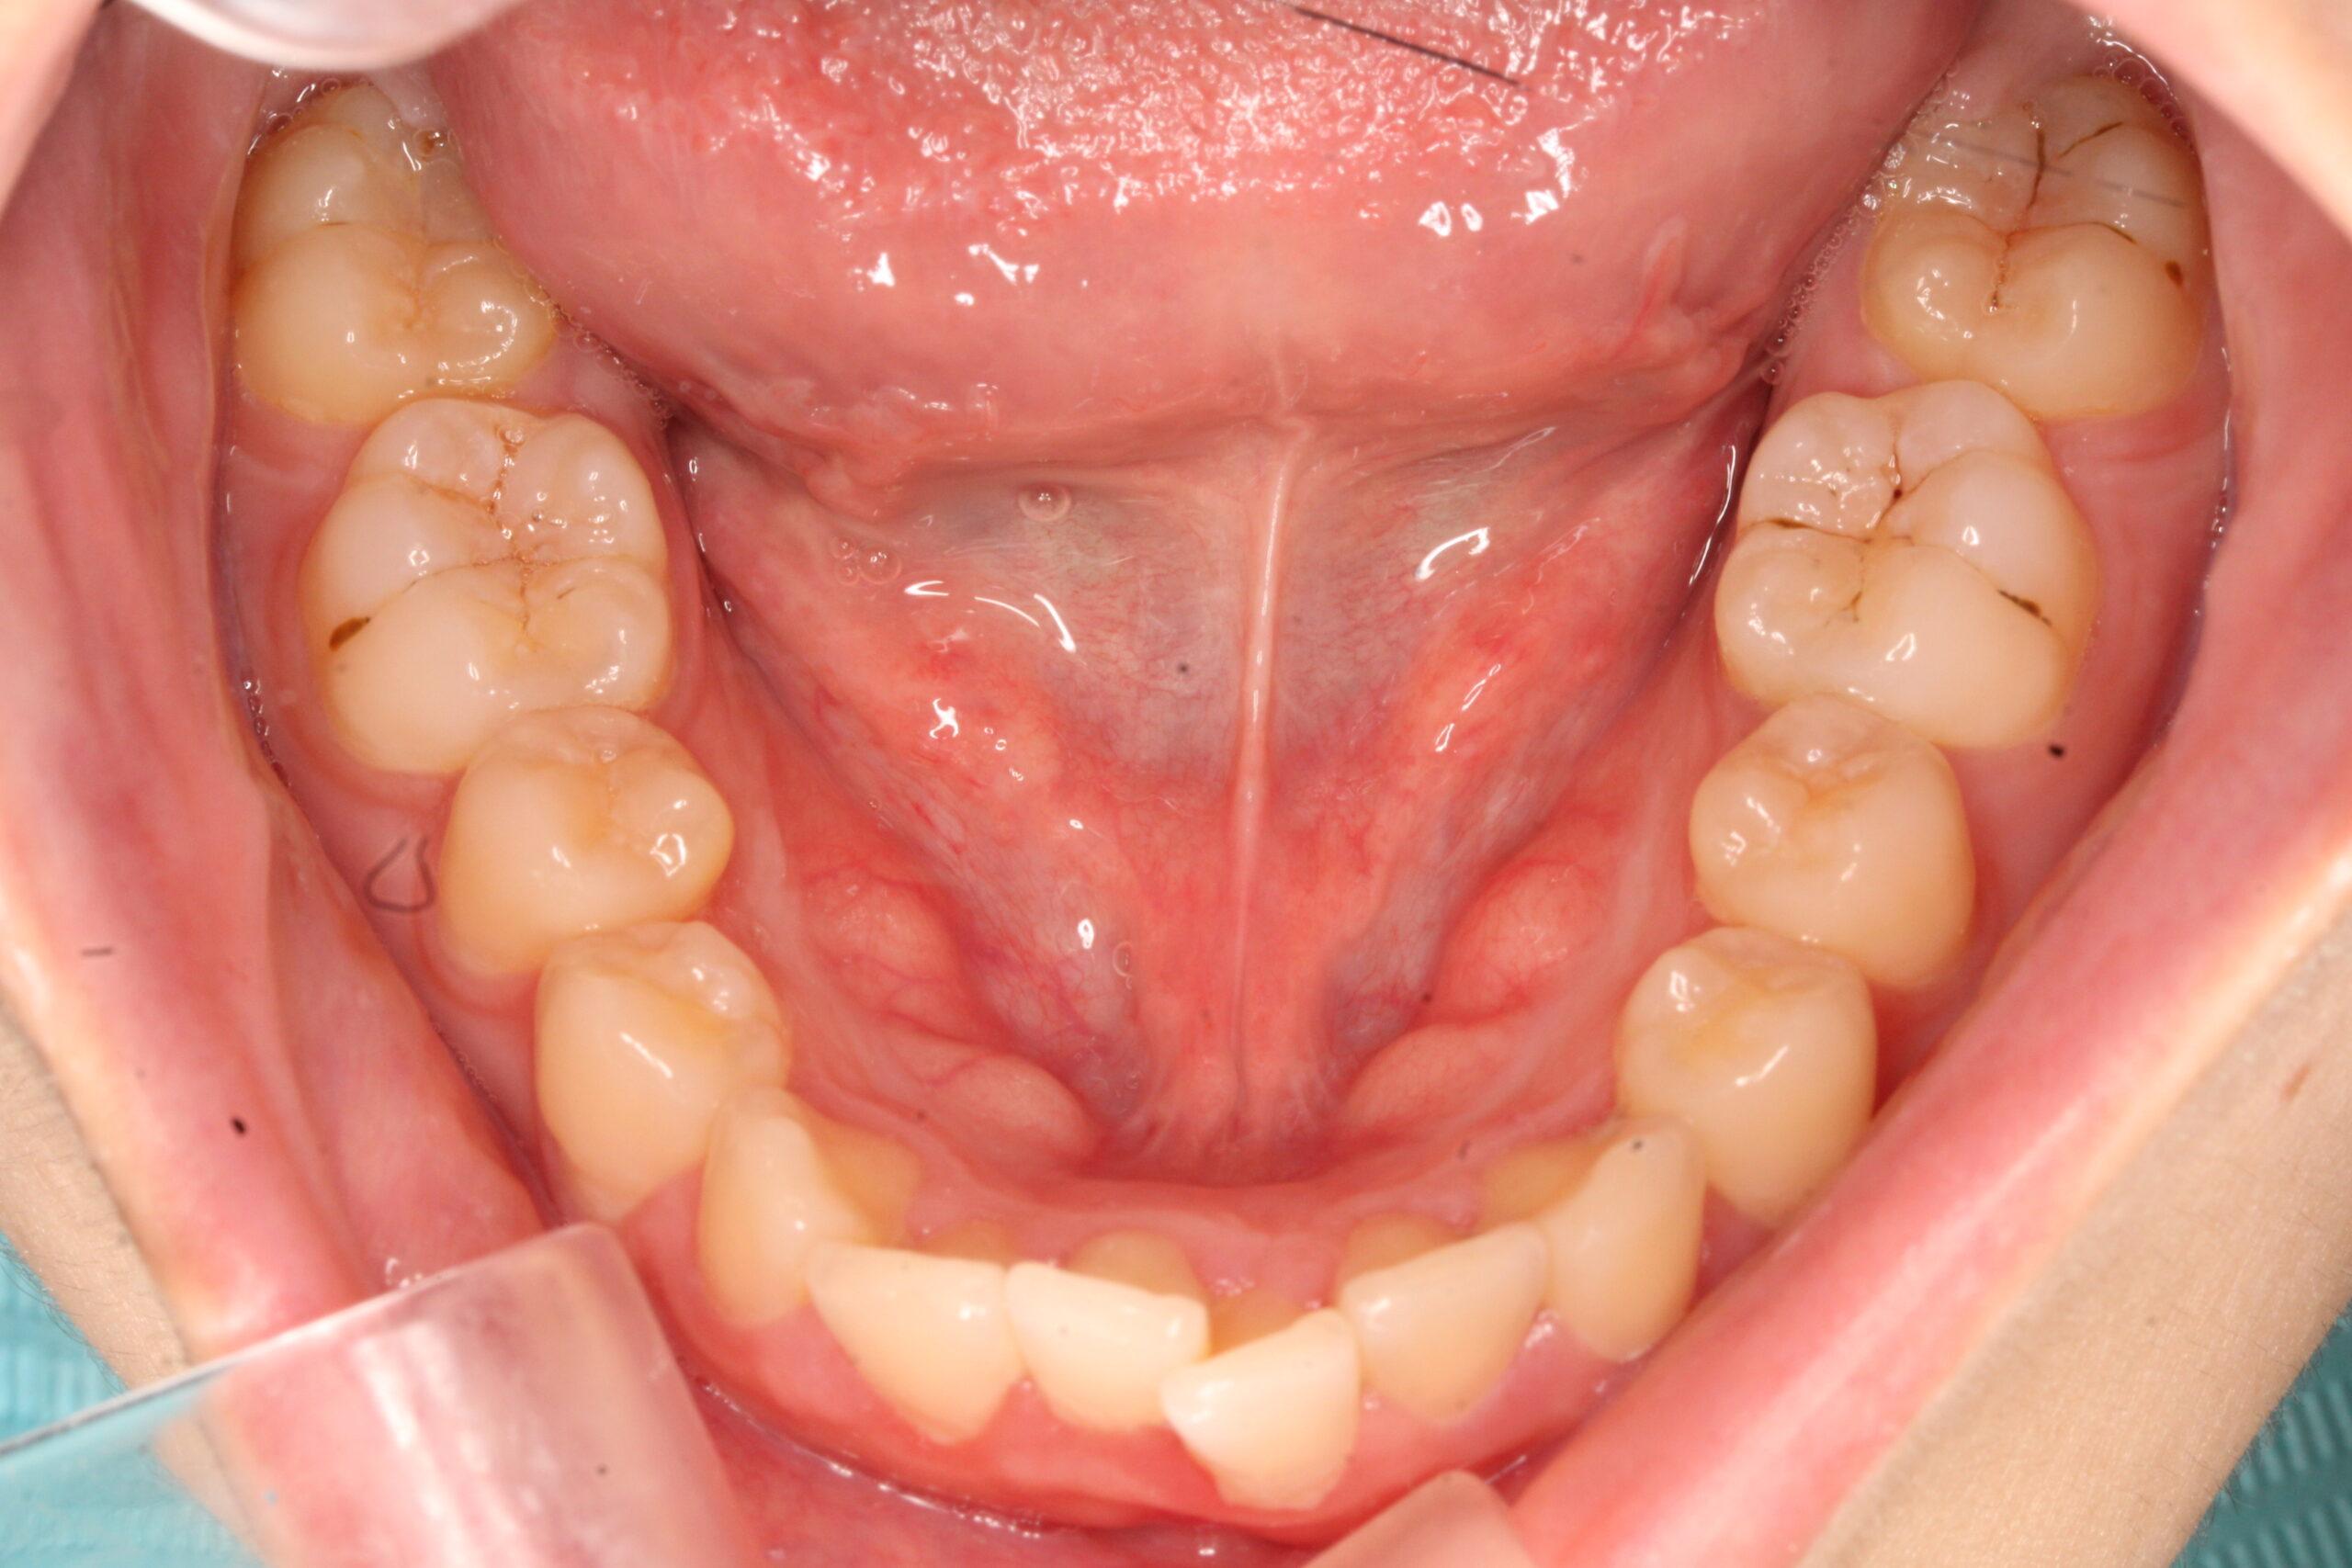

矯正術前:上顎

矯正術後:上顎